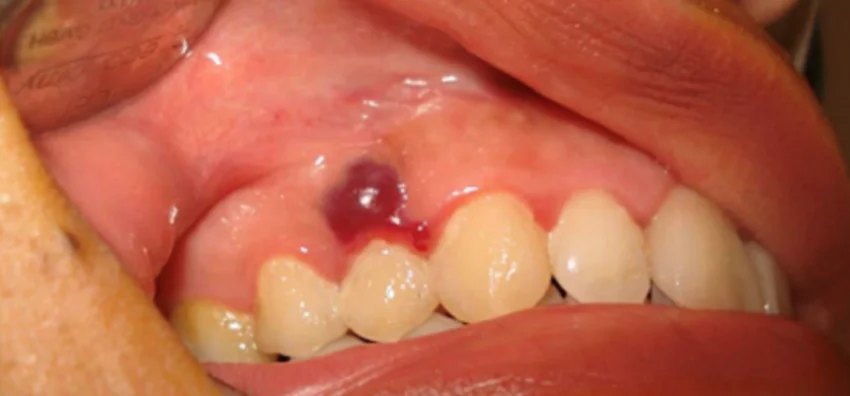

- Hemangioma és egyéb éreredetű elváltozások (pl. venosus malformatio, varix) – kékes-lilás, nyomásra változó képlet.

Szájüreg, garat vagy gége beningus tumor eltávolítása

Szájüregi hemangioma